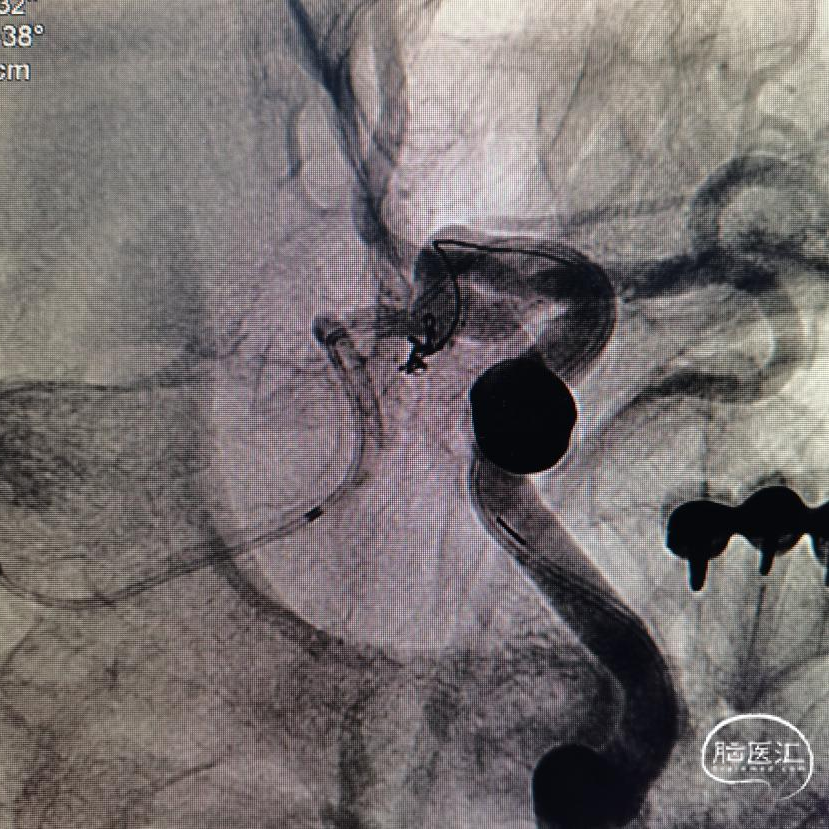

第二次

两次角度就差了一点点,结果截然相反,真是个“差之毫厘谬以千里”啊。剩下的工作就简单了。

圈已到位,准备压个支架。在后交通动脉起始处再放个圈,加强防护,防止复发。